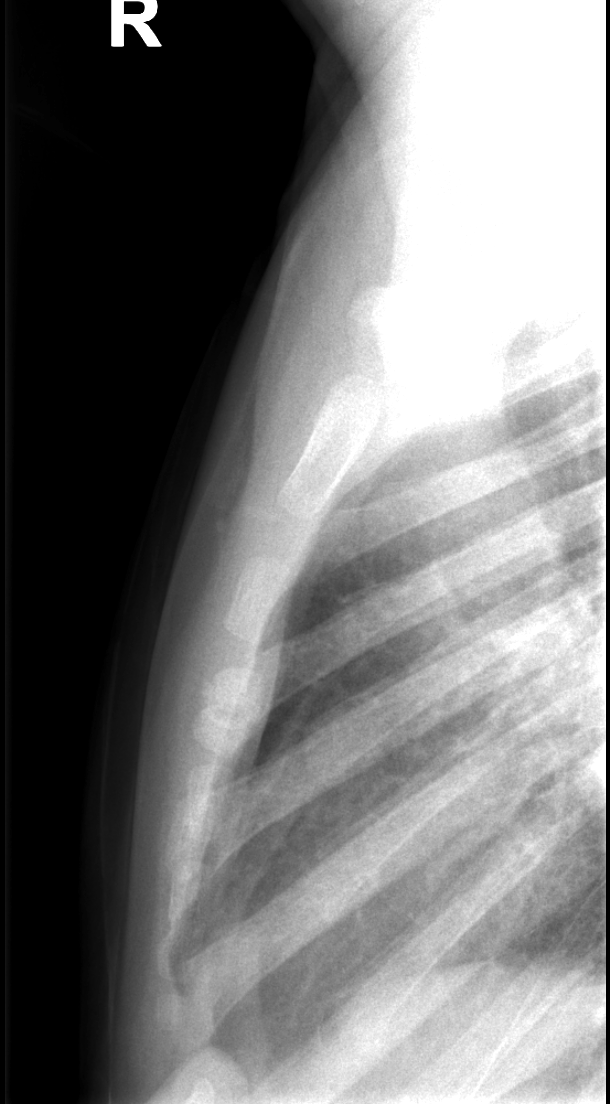

Section 1 Submit Findings CB1550 Findings Skeletal Survey - Technique Check Skull AP/Lat Yes No Cervical and Thoracolumbar spine Yes No Chest X-Ray Yes No Ribs – Left/Right Oblique Yes No Abdominal X-Ray Yes No Pelvis with both hips Yes No Bilateral Humerus, Forearm, Hand Yes No Bilateral Femur, Tibia/fibula, feet Yes No Any additional lateral views of the extremities Yes No The exam is over or under penetrated. Yes No The exam may or may not be limited by overlying structures or soft tissues, body habitus, patient positioning, support devices, or motion. Yes No The area of concern is indicated by the patient, technologist, or care provider. Yes No The area of concern is included on the exam. Yes No Soft Tissues There is soft tissue swelling, indistinctness of fat/muscle planes, gas, or laceration in the area of clinical concern. Yes No There is an effusion, fat pad displacement, or fat fluid level. Yes No There is a radiodense or lucent foreign body. Yes No There are other densities, calcifications, post-surgical changes, or support devices in the soft tissues. Yes No Any support lines/tubes. Yes No Bone There is a break or interruption of the continuity of the cortical or cancellous bone. Yes No There is overriding of the trabeculae with apparent sclerosis. Yes No There is displacement of a fracture fragment. Yes No There is bowing of the bone in addition to the fracture at the apex of the bowed bone concerning for the greenstick. Yes No There is a spiral fracture of the leg concerning for toddler’s fracture. Yes No There is abnormal angulation or bulging of the cortical surface relative to the normal cortex which could be from a buckle or torus fracture. Yes No There is a displaced fragment which may be from avulsion by a tendon, ligament, or joint capsule or from a comminuted or other fracture. Yes No The stress trabeculae or other trabeculae of the cancellous bone are interrupted or otherwise abnormal. Yes No There is subperiosteal or endosteal reaction which could indicate a healing or subacute fracture or other abnormality. Yes No There is hard/soft callus formation. Yes No There is remodeling of the bone. Yes No There is a corner fracture or metaphyseal lesion that could be from nonaccidental trauma. Yes No There are multiple fractures of different ages. Yes No There are vertebral body/spinous process fractures. Yes No There are rib fractures. Location - posterior or lateral. Yes No There is scapular/sternal fracture. Yes No There are fractures of the digits. Yes No There are wormian bones. Yes No There are intrasutural bones. Yes No There is metaphyseal abnormality (lucencies, increased density, erosion) which may be from something other than injury such as stress, metabolic disease (e.g. rickets with loss or distortion of the zone of the provisional calcification), neoplasm (e.g. leukemia), heavy metals, inflammation, or infection. Yes No There are metaphyseal spurs. Yes No There are bony deformities involving multiple bones. Yes No The bones are gracile. Yes No There are non-healing fractures. Yes No There is/are focal or multifocal lytic/lucent, blastic/sclerotic or mixed density lesion(s) or other abnormality. Yes No Overall bone density is increased or decreased with or without thinning or thickening of the cortical or cancellous bone. Yes No Growth plates, ossification centers, apophyses The growth plate(s) is/are abnormal. Yes No There is widening of the physis from a fracture with or without displacement of the epiphysis (Salter-Harris I). Yes No There is a fracture through the physis which then extends into the metaphysis with or without angulation or displacement (S-H II). Yes No There is a fracture through the physis which then extends into the epiphysis and is intra-articular, with or without angulation or displacement (S-H III). Yes No There is a fracture through the metaphysis, physis, and epiphysis which extends into the joint space with or without angulation or displacement (S-H IV). Yes No There is narrowing of the physis from a compression fracture (S-H V). Yes No The apophysis, epicondyle, secondary ossification center, or accessory ossicle is displaced or otherwise abnormal. Yes No The ossification centers are underdeveloped. Yes No Joints and alignment There is an effusion, fat pad displacement, or fat fluid level. Yes No The epiphysis or subchondral bone is fractured, interrupted, flattened, compressed, impacted, displaced, or otherwise abnormal. Yes No There is an intra-articular loose body or chondrocalcinosis. Yes No The joint is widened, narrowed, dislocated, malaligned, or incongruent. Yes No There is pseudoarthrosis. Yes No Other findings There are developmental changes or other anatomic variants or other existing conditions that may or may not be contributing to symptoms which can or should be further evaluated non-emergently or are otherwise incidental. Yes No The remainder of the exam is abnormal for age. Yes No The lungs show focal airspace opacity. Yes No There is pneumothorax. Yes No There is organomegaly. Yes No There is intra-abdominal calcification. Yes No There is displacement of the bowel loops. Yes No There is free intraperitoneal air. Yes No The bowel loops are dilated/obstructed. Yes No There is paraspinal soft tissue abnormality. Yes No